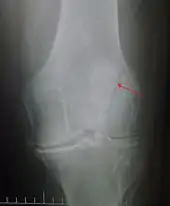

The patella can break in various ways depending on the way it is injured, and into two or more pieces.[1] Types include transverse, with one fracture line and is the most common type,[5] marginal, osteochondral and the rare vertical type, or stellate, where a direct compression force gives rise to a comminuted pattern.[5][7] Patella fractures can be further classified as displaced, where the broken ends of bone do not line up correctly and separate by more than 2mm, or undisplaced and stable where pieces of bone remain in contact with each other.[1][7] If fragments of patella bone stick out from the skin it is known as an open patella fracture, and closed if the overlying skin is intact.[1]

Transverse fracture of patella

Comminuted fracture of patella

Osteochondral fracture of patella

Vertical patella fracture